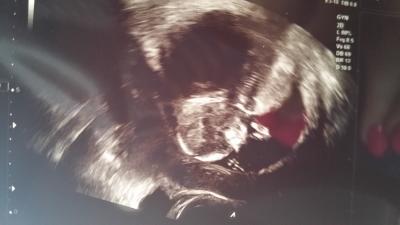

Jetzt nochmal... irgendwie wollte der erste Eintrag nicht ^^ Also Baby gehts gut .... hat fleußig gewunken abbber seine kleinen Beinchen gekreuzt so das wir unsere neugierde noch nicht nachgeben konnten hahahahaha

Bild zu Foto vom Fa - Forum für März - Mamis